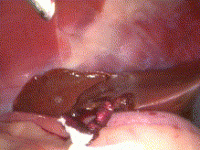

Since 1999, when the author first described the research and potential applications of minimally invasive gastrointestinal surgery in animals, veterinarians have begun to apply some of these techniques in treating client owned animals. Minimally invasive surgery is advocated with diagnostic, prophylactic, and therapeutic intent. There has been a transition from a minimally invasive caseload toward the expansion of diagnostic procedures, adoption of prophylactic procedures (such as lap-assisted gastropexy), and performing more difficult therapeutic procedures. Small animal patients benefit from reduced tissue trauma and experience a rapid recovery. In this article, current research and minimally invasive gastrointestinal procedures in animals are discussed.